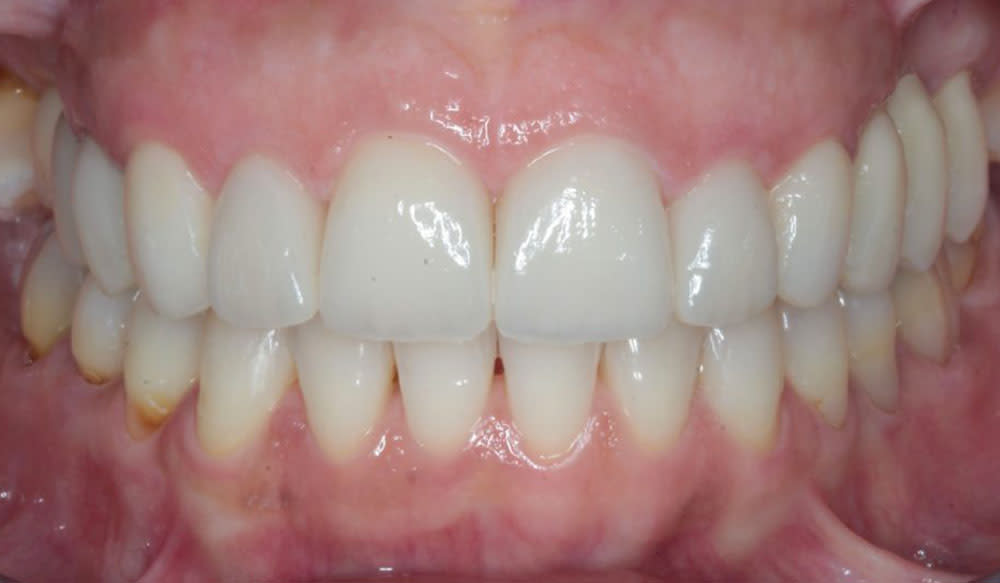

Cắn sâu

Cắn sâu là tình trạng mà sự phủ theo chiều dọc của các răng cửa ở khớp cắn trung tâm lớn hơn 30 – 40%.

Thông tin bệnh nhân:

Tuổi: 13

Giới tính: Nam

Lựa chọn điều trị Invisalign: Invisalign Comprehensive

Tổng thời gian điều trị:

24 tháng